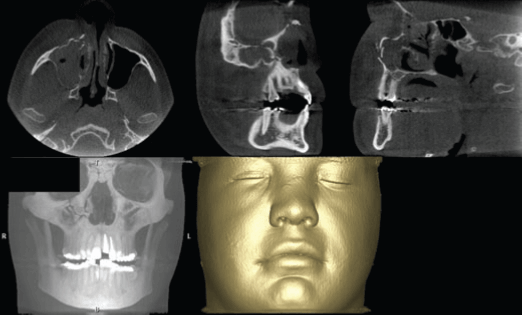

El examen por imágenes es un componente esencial del manejo de eventos traumáticos. Respalda todos los aspectos, desde el diagnóstico y la planificación del tratamiento hasta la evaluación de los resultados. Desafortunadamente, la cantidad de información obtenida de las radiografías simples convencionales o capturadas digitalmente es limitada por el hecho de que la anatomía tridimensional del área que se visualiza se comprime en una imagen bidimensional. Como resultado de la superposición, las radiografías bidimensionales revelan aspectos limitados de la anatomía tridimensional, lo que requiere, en varias ocasiones, la combinación de diferentes radiografías convencionales. Estos problemas se superan fácilmente utilizando técnicas de imagen que pueden producir rápidamente imágenes tridimensionales de las estructuras afectadas y los tejidos circundantes. Las ventajas de la tomografía computarizada (TC) médica tridimensional ya están bien establecidas en muchas especialidades odontológicas. También se ha utilizado en pacientes que requieren reconstrucción facial quirúrgica, cirugía ortognática, implantes dentales y extracciones complicadas. La alta dosis de radiación, el coste, la disponibilidad limitada y cierta dificultad en la interpretación han dado lugar a un uso limitado de las imágenes de TC como herramienta diagnóstica definitiva. Las recientes innovaciones en la tecnología de TC de haz cónico han invertido recursos para abordar estas cuestiones y podrían alterar sustancialmente la forma en que los pacientes que tienen traumatismos potencialmente complejos.

La parte media de la cara comprende los huesos nasal, maxilar y cigomático. Las fracturas en esta región afectan a estructuras que rara vez se fracturan por sí solas, pero que pueden dar lugar, en la mayoría de los casos, a fracturas multifragmentarias o complejas. Estas estructuras son capaces de soportar una fuerza considerable desde abajo, pero son relativamente fáciles de fracturar como resultado de fuerzas normales aplicadas desde otras direcciones. A diferencia de la protección rígida de la mandíbula, las fracturas de la parte media de la cara pueden afectar a varias estructuras importantes, incluida la base del cráneo, que pueden no evaluarse adecuadamente con las imágenes convencionales. La TCCB es capaz de mostrar un mayor número de líneas de fractura y fragmentos en comparación con las imágenes convencionales, representando con precisión la posición y la orientación de los fragmentos desplazados en un intervalo de tiempo razonablemente corto. Clásicamente, los estudios de Rene Le Fort han sido la base para clasificar estos tipos de fracturas ofrecieron una excelente revisión de estas fracturas.

Consideradas comunes en pacientes tras traumatismos faciales contusos, las fracturas del complejo cigomático maxilar son las segundas fracturas faciales más frecuentes después de las fracturas nasales y pueden afectar a las suturas cigomático-frontal, cigomático-temporal y cigomático-maxilar, con fracturas a lo largo de los cigomáticos, el suelo orbitario y el maxilar, lo que da lugar a fracturas trimalar o trípode. Los huesos frontal, etmoidal, palatino, esfenoidal y temporal también pueden verse afectados. En la mayoría de los casos, el seno maxilar se llena de sangre y requiere una intervención en la región periorbital como consecuencia de la fractura de las paredes orbitales. La inflamación de los tejidos blandos asociada al traumatismo puede enmascarar las fracturas cigomáticas, lo que indica la necesidad de realizar imágenes para descartar cualquier afectación de estas estructuras. La TCCB está especialmente indicada porque es capaz de proporcionar excelentes imágenes de las estructuras óseas afectadas y es eficaz para detectar fracturas ocultas o sospechosas antes de la reducción y fijación quirúrgicas.